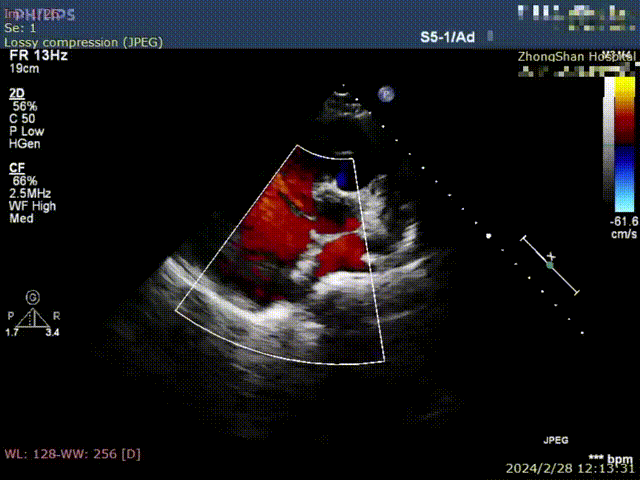

葛均波院士为患者植入FreeFlow经皮房间隔分流器,在DSA的监测下分流器左盘通过输送鞘管到达左心房并释放;回撤输送鞘管,释放分流器右盘;行牵拉试验,观察分流器形态、位置、左右心房分流情况;旋转输送钢缆将分流器完全释放;撤离输送钢缆、输送鞘管,手术圆满完成,分流器释放性能、输送系统操作性能均表现良好。复查心超/DSA,分流器位置、大小、形态合适,对周围结构无影响,清晰可见右向左分流。

心超检查右向左分流

术后24小时观察显示患者生命特征平稳,心电监测未见心律失常,术前氧饱和度是95%,术后氧饱和度是98%;心脏彩超可见分流器位置细束房水平分流,患者自诉感觉良好,无特殊不适。